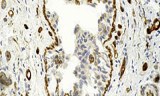

Tissue sections are thin slices of biological tissue prepared for microscopic examination and molecular analysis, fundamental in histopathology, molecular biology, and biomedical research. These sections enable detailed visualization and localization of cellular structures, DNA, RNA, and protein markers, facilitating the study of normal and diseased tissues.

- Localization and identification of mRNA and protein markers within specific tissue contexts.

- Study of gene and protein expression patterns in normal and pathological tissues.